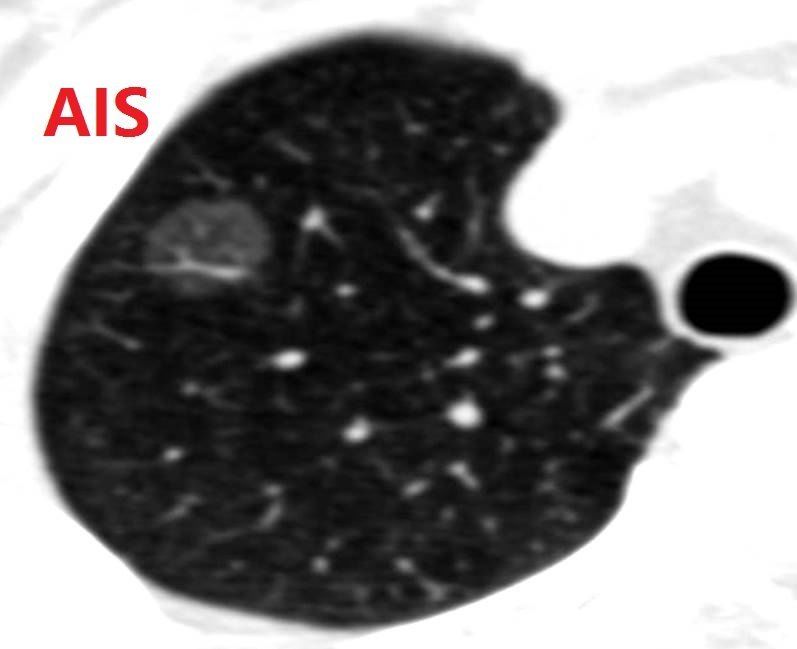

AIS,adenocarcinoma in situ,就是原位腺癌。肺原位腺癌指的是发生在支气管粘膜或肺上皮层,没有突破基底膜的病变。虽然名字中有癌,但WHO的肺癌最新分类中,肺原位癌也和非典型腺瘤样增生一样,被划入腺体前驱病变。原位腺癌一般肿瘤直径比较小,1cm以内居多,也有1cm以上的,很少超过2cm,CT上大多数为纯磨玻璃结节,少数为含实性成分的混合磨玻璃结节。在TNM分期中,肺原位癌为0期,手术治愈率为100%,术后病理细胞亚型一般为贴壁型。

原位癌生长极其缓慢,呈惰性生长,有的可能随访5-10年大小、形态、密度都没有任何变化。恶性征象不明显,而且手术就能治愈,正因为此,原位腺癌被划入腺体前驱病变,让很大一部分病人心理上得到安慰。同时,也告诉大家原位癌阶段不要急着手术,在安全范围内随访观察,可以避免因一个几毫米的结节去手术而早早的丧失一部分肺功能。